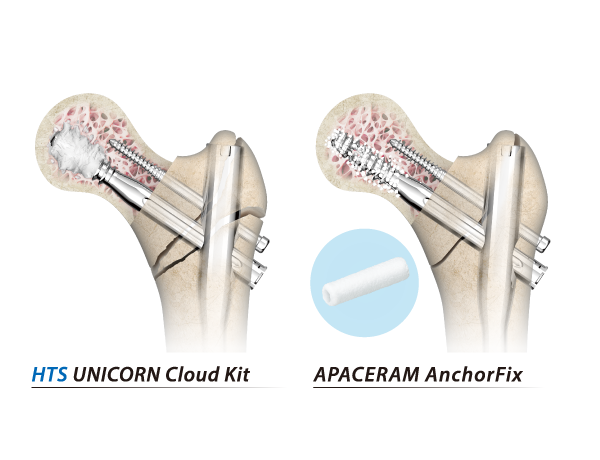

- UNICORN Cloud Kit

- Anchor Fix